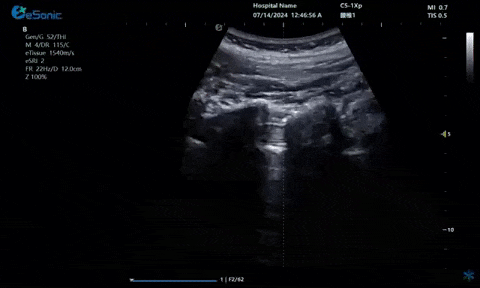

超声引导下肋间神经阻滞切面